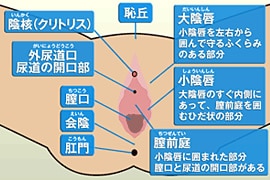

女性器について 正しい知識を持ちましょう ゆかりレディースクリニック 神戸市三宮にある婦人科

会陰 えいん は 腟口 ちつこう から肛門までを指します。 生殖器は発生学的由来により内生殖器と外生殖器に分けられます。外陰部は体表の皮膚が変化して生じた外生殖器で、外からの刺激に対して生殖器を守る役割があります。会陰部に近いほど男性化不全の程度が強い 4.陰嚢の形成は? 低形成、二分陰嚢の有無 <Quigley分類> 完全男性型 完全女性型 図:たのしく学ぶ小児内分泌より 外陰部の診察:女児の男性化 1.陰核の大きさは? 横径を計測することが多い。 >7 mm → 陰核肥大 2.膣口は確認できるか? 3.陰唇動画あり出張オイルリンパマッサージの四ツ目本舗は東京都心部のホテル・自宅へ、深夜1時迄、出張オイルリンパマッサージを提供。「no sokeibu, no life紙パンツを捨てよう!」当店の「鼠径部(そけい部)オイルリンパマッサージ」の「会陰部について」の説明

会陰 ( えいん )とは、 解剖学 において、狭義では 外陰部 と 肛門 の間、広義では左右の 大腿 と 臀部 で囲まれる 骨盤 の出口全体をさす。 恥骨結合 と左右の 坐骨結節 、 尾骨 を結ぶ菱形部となる。会陰と残尿感の解消には、 一体どのような関係性があるのでしょうか。 男性は蟻の門渡りを押すことで残尿感を解消できるのか? 排尿を終えた直後なのに「まだ膀胱内に尿が残っているような気がする、 なんだかスッキリしない」という不快感を覚える 男性の陰部のかゆみの原因として考えられる疾患とは? 男性の陰部にかゆみの症状があるとき、大まかな原因としては「性感染症」「皮膚疾患」の2つの場合が考えられます。 かゆみのある性感染症としては「性器ヘルペス・尖圭コンジローマ・梅毒」などがあり、どれも性行為により感染する可能性があります。 性器ヘルペスでは、陰部に水膨れができ

会陰部 広義の会陰の定義 (会陰部も参照) 前方の陰丘、外側の大腿内側面、後方の殿溝と殿間裂の上縁に挟まれた菱形の領域 (M) 狭義の会陰の定義 男性の場合尿道と会陰の間、女性の場合膣と肛門の間を指す (KH237) WordNet the general region between the anus and the男性の会陰は前後径5~6センチメートル、女性では2~3センチメートルである。 この部分の皮膚の正中線には色素に富んだ会陰縫線 (ほうせん)があり、男性では陰嚢縫線に続く。 会陰部皮下には脂肪組織、平滑筋線維が多く存在し、その深部には横紋筋からなる会陰筋層がある。 骨盤腔 (こう)を上方からみると、骨盤下口を会陰筋が筋膜、腱膜 (けんまく)とともに会陰部のヘルニアについて情報をまとめました。 ヘルニア治療辞典 男性と女性では、起こる場所が異なると言われていますが、女性の方がかかる率が高くなっています。 恐らく、女性は妊娠や出産などがあるため、会陰部が大きく収縮することが原因の1つではないかと考えられます。

女性器について 正しい知識を持ちましょう ゆかりレディースクリニック 神戸市三宮にある婦人科